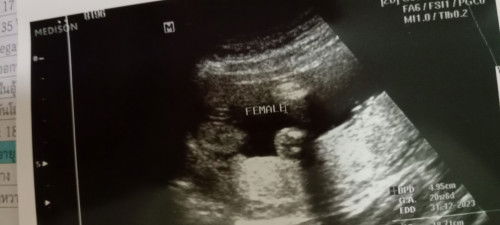

เเบบนี้ หญิง หรือว่าชายค่ะ #ขอบคุณล่วงหน้านะคะ

female= หญิง ค่ะ

เพศลูก จากผลอัลตร้าซาวด์ ♥️👶🫄

ขออนุญาตสอบถามคุณเเม่ๆ ที่มีประสบการณ์ทั้งหลายนะคะ คุณเเม่เห็นเป็นเพศอะไรกันเอ่ย ไปซาวมา คุณหมอบอก ได้ลูกสาวค่ะ 🥰#ขอบคุณล่วงหน้านะคะ #ขอบคุณสำหรับคำตอบค่ะ #ท้องเเรกค่ะ

ยินดีด้วยค่า 🎉